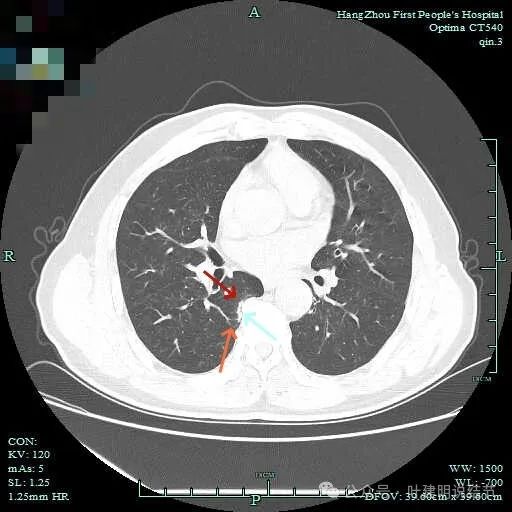

上图呈结节状,表面不平,有少许磨玻璃成分。

结节状,密度高,边缘欠光滑。

与脊柱之间有间隙,表面有细毛刺。

表面不平,似有细支气管截断征。

边缘不平毛糙。

像慢性炎似的。

瘤肺边界欠清。

边缘区淡磨玻璃密度。

1、诊断问题:主病灶是挺典型的恶性表现,而且应该是浸润性腺癌了的,当然不是太致密,仍是早期的可能性大;次病灶纵观应该是片状的,但局部有结节状,结节状的地方,表面不平毛糙,有细毛刺,有血管征,有细支气管截断的样子,此灶感觉不太舒服,但说不是必为恶性。其他结节不确切且风险低,目前不需要管。